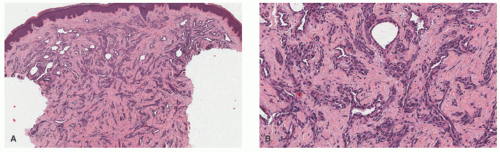

demonstrates increased fibrosis and diminished vascular lobules. Deep dermal or subcutaneous presentations of PG are not uncommon and may be intravascular. Intravascular PG presents within the lumen of a vein or artery. Intravenous PG was originally described by Cooper et al. in 1979,18 as an intraluminal polyp comprised by lobules of capillaries lined by flattened or rounded endothelial cells (Figure 25-7B). A surrounding fibrous stroma is also usually observed.19,20

lymphoid follicles) and a lesser vascular element. More cellular EH types may mimic malignant tumors such as epithelioid hemangioendothelioma (EHE) or even epithelioid angiosarcoma (AS) (Figure 25-9C). Immunohistochemistry and molecular studies such as fluorescent in situ hybridization (FISH) can be helpful in ruling in these malignant tumors, because 90% of EHE demonstrate a characteristic WWTR1-CAMTA1 fusion, which results from a t(1;3)(p36;q25) translocation,29 and many ASs demonstrate MYC amplification on FISH and/or MYC-positivity on immunohistochemistry.30